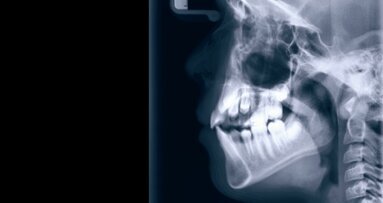

Diabetes, eine Erkrankung, die durch entzündliche Prozesse beeinflusst wird, stellt ein bedeutendes globales Gesundheitsproblem dar. Parodontitis, eine weitverbreitete Zahnfleischerkrankung, kann systemische Entzündungen hervorrufen, die möglicherweise zur Entstehung von Diabetes beitragen. Dr. Tae-Jin Song von der Ewha Womans University College of Medicine in Seoul, Südkorea, und sein Forschungsteam untersuchten Daten von 188.013 Teilnehmern des National Health Insurance System-Health Screening Cohort (NHIS-HEALS) aus den Jahren 2003 bis 2006. Diese umfassten demografische Informationen, Krankengeschichte, Mundhygienegewohnheiten sowie zahnärztliche Befunde.

Die Studie ergab, dass 17,5 Prozent der Teilnehmer an Parodontitis litten. Innerhalb von zehn Jahren entwickelten 16 Prozent (31.545 Personen) Diabetes. Nach Berücksichtigung von Faktoren wie Alter, Geschlecht, Gewicht, Blutdruck, sozioökonomischem Status, Lebensstil und Krankengeschichte zeigte sich, dass Parodontitis sowie der Verlust von 15 oder mehr Zähnen das Risiko für Diabetes um neun Prozent bzw. 21 Prozent erhöhten. Im Gegensatz dazu verringerte sich das Risiko bei dreimal täglichem Zähneputzen oder häufiger um acht Prozent.

Eine detaillierte Analyse nach Altersgruppen zeigte, dass bei Erwachsenen bis 51 Jahren das zweimal tägliche Zähneputzen das Diabetesrisiko um 10 Prozent und dreimal tägliches Putzen um 14 Prozent senkte, im Vergleich zu denen, die nur einmal täglich oder seltener putzten. Bei Personen über 52 Jahren reduzierte das zweimal tägliche Zähneputzen das Risiko nicht signifikant, doch dreimal tägliches Putzen senkte es um sieben Prozent. Parodontitis hatte einen stärkeren Einfluss auf jüngere Erwachsene, die ein um 14 Prozent erhöhtes Risiko aufwiesen, während bei älteren Erwachsenen das Risiko um sechs Prozent erhöht war. Jüngere Menschen mit bis zu sieben fehlenden Zähnen hatten ein um 16 Prozent höheres Risiko, während ältere Erwachsene mit 15 oder mehr fehlenden Zähnen ein um 34 Prozent erhöhtes Risiko aufwiesen.

Zudem wurden geschlechtsspezifische Unterschiede festgestellt: Frauen, die dreimal täglich putzten, hatten ein um 15 Prozent geringeres Diabetesrisiko, während das Risiko bei denen, die zweimal putzten, um acht Prozent niedriger war im Vergleich zu Personen, die nur einmal täglich oder seltener putzten. Bei Männern reduzierte dreimal tägliches Zähneputzen das Risiko um fünf Prozent, wobei kein signifikanter Unterschied zwischen zweimal und einmal täglichem Putzen festgestellt wurde.

Obwohl die genaue Beziehung zwischen Mundhygiene und Diabetes noch nicht vollständig geklärt ist, deutet die Studie darauf hin, dass Karies und Parodontitis zu chronischen Entzündungen führen könnten, die wiederum zur Insulinresistenz und letztlich zu Diabetes beitragen können.

Zusammenfassend lässt sich sagen, dass eine sorgfältige Mundhygiene entscheidend zur Verringerung des Diabetesrisikos beitragen kann, während mangelhafte Zahnpflege und Zahnkrankheiten dieses Risiko erhöhen. Die Optimierung der Mundhygiene könnte daher ein wichtiger Ansatz zur Prävention von Diabetes sein.